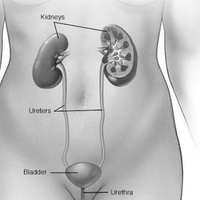

Инфекции мочевыводящих путей – состояние инфицирования мочевыводящего тракта микрофлорой, которая вызывает его воспаление.Различают инфекцию верхних (пиелонефрит) и нижних мочевых путей (цистит, простатит, уретрит) по наличию или отсутствию симптомов (симптоматическую или бессимптомную бак-териурию), по происхождению инфекции (внебольничную или нозокомиальную), осложненные и неосложненные.

Осложненные инфекции сопровождаются функциональными или анатомическими аномалиями верхних или нижних мочевых путей.